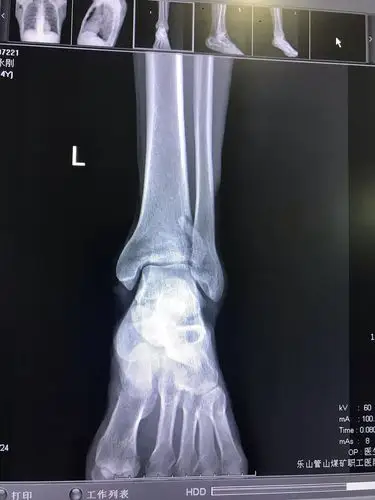

Ⅱ(旋前外翻外旋骨折)当足呈旋前位,外翻和外旋的外力打击胫骨远端

右胫腓骨远端骨折

胫腓骨远端双侧骨折不知道多久能重回绿茵现在已

胫腓骨远端粉碎性骨折